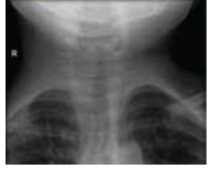

Thumb sign seen in